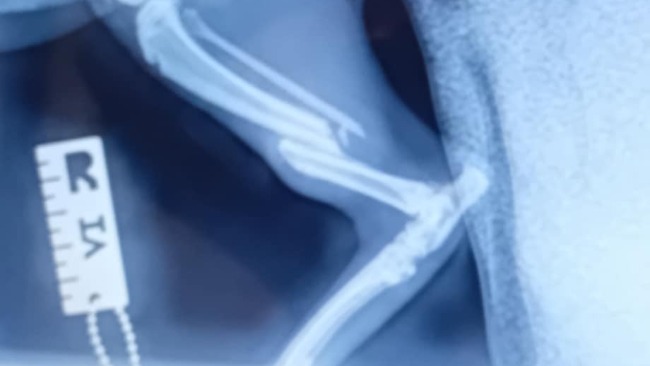

Czesc nazywam sie Szymon postanowilem zalozyc zbiorke na naszego kotka Pedra . W lipcu przyblakal sie obcy kotek i krecil wokol domu okolo tygodnia , zauwazylismy ze kotek jest wychudzony wiec postanowilismy go zaadoptowac i o niego zadbac . Niestety pedro mial ostatnio wypadek i proces leczenia kota jest kosztowny , Bardzo prosze o wplacanie choćby 5 zlotych na pedra bardzo nam to pomoze , Dziekuje <3